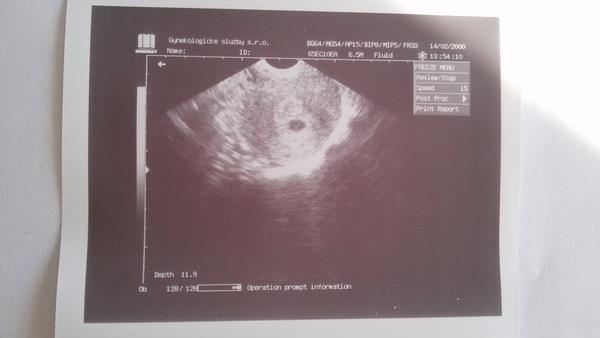

@veroniquecz Mě to hodně sebralo, protože jsem tohle vážně nečekala, navíc když jeho ultrazvuk i u prvního těhotenství ukazoval stáří velmi odlišně od ostatních (syn byl dle jeho UTZ mladší než skutečně byl), hcg v krvi mi stouplo v normě, co jsem si vypočítala, špinit už ani nešpiním, jen jsem z toho psychicky rozhozená. V pondělí bych zašla ještě na krev, abych viděla, jestli narůstá hcg. A mám v plánu zajet zítra do nemocnice, na pohotovost, na kontrolu, kde by mě zkontrolovali tím lepším ultrazvukem... A jinak bych samozřejmě ještě počkala. Přikládám ještě fotku z úterý, od mého gyndr., která ale vůbec není tak kvalitní, jakou si založili do dokumentace v nemocnici na pohotovosti v minulou sobotu. Fotka z úterý - stejný nález na stejném přístroji i v pátek...

Tak změna... Ráno jsem vstala, šla na WC, kde ze mě šla tmavá krev i světlá ke konci, v noci jsem měla bolesti, tak jsme vyrazili na pohotovost a já už opravdu byla připravená na nejhorší, když jsem krvácela. Doktorka se mi ptala na kontrolu v týdnu u OG, to jsem řekla, že jsem nebyla, vyšetřila mě opravdu pečlivě - nejlepší gynekoložka, kterou jsem snad kdy potkala, empatická, po vyšetření pohmatem, že udělá ještě UTZ, že to krvácení vypadá normálně, že se to v těhotenství stává (a já pořád čekala na to, až mi oznámí to nejhorší), kouká na UTZ a povídá: No a tady je také vše v pořádku.. Já překvapeně, jak v pořádku? Ukázala mi ultrazvuk, bijící srdíčko!!!! 🙂 Vývoj naprosto normální, GV i žloutkový váček, srdíčko ťukalo jak o život, odpovídá 6+2 (minulou sobotu 5+4 tt, teď 6+2 tt takže úplně vývoj v normě! a to mi gynekolog v pátek říkal 4+6!). Začala jsem plakat radostí,.... Nedá se slovy popsat, jak jsem šťastná, děkovala jsem i tomu nahoře, ač nejsem věřící. Mám v plánu změnit gynekologa.

@michaelasm krasne zauzleni a pevne verim, ze vse dotahnes v poradku az do konce. Co se tyce odpovidacijich tt, na zacatku se to opravdu moc spatne meri, protoze tam staci netrefit se o mm a uz jsi v jinem tydnu. A co lekar, nameri to jinak. To srdicko je uzasne!